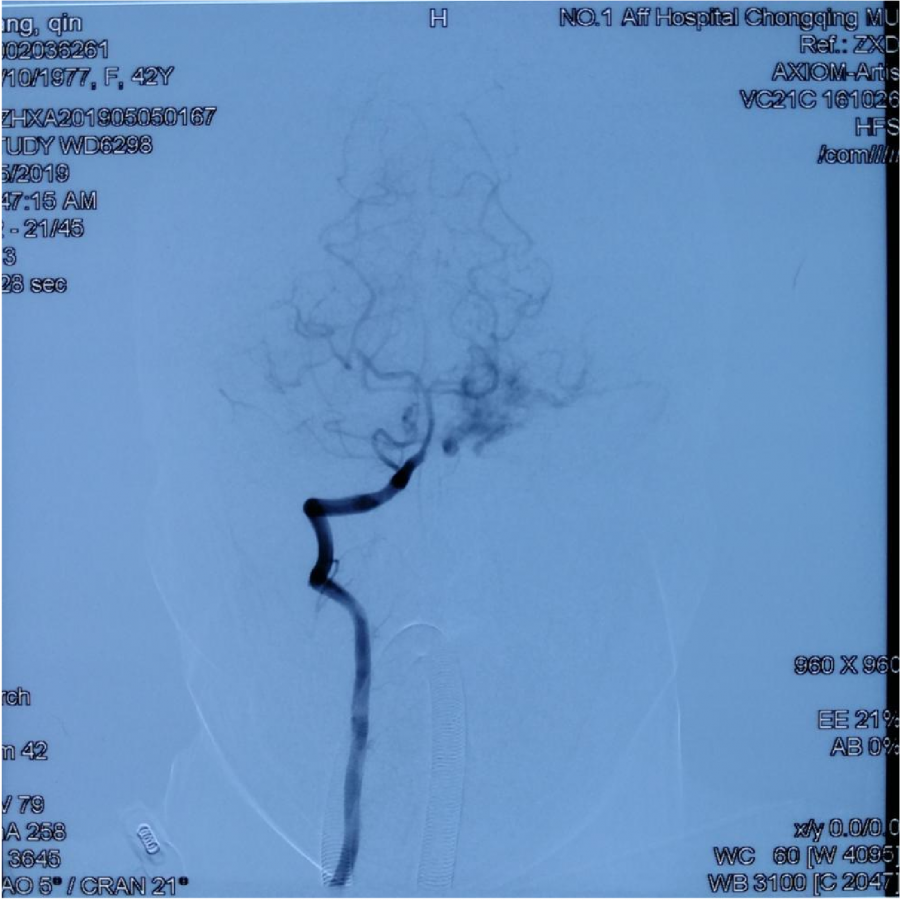

本次⼊院⾏DSA检查:PICA供⾎区有畸形⾎管团,引流到横窦